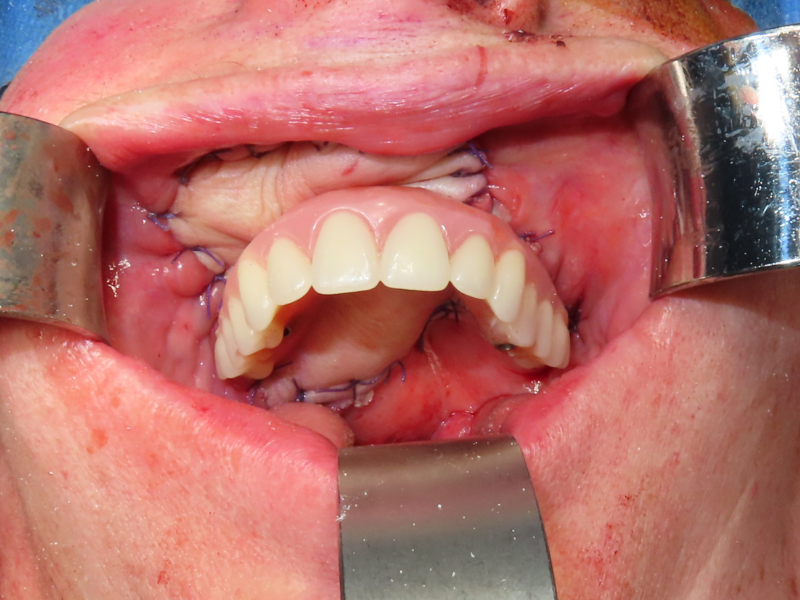

Prosthesis Fabrication & Loading

Creating and fitting your new teeth

Impressions for your new teeth are taken either during surgery or in the early days of your recovery. This allows the dental laboratory to begin fabricating your fixed prosthesis (bridge) while you're still in the initial healing phase.

Remarkably, your new fixed teeth can typically be fitted within 3-4 weeks of surgery—far faster than traditional approaches which often require many months. This rapid rehabilitation means you can eat, speak, and smile with confidence much sooner.

The prosthesis is securely attached to your implants but can be removed by your dental team for cleaning and maintenance. To you, it looks and functions like natural teeth.

Prosthesis Fabrication - Fixed dental prosthesis fitting